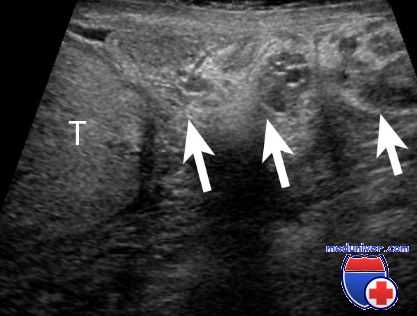

В тех случаях, когда нужно длительно орошать вскрытый инфицированный очаг, применяют дренажи из резиновой или синтетической эластической трубки необходимой длины, диаметром 3—8 мм. Один из концов трубки косо срезают и закругляют острые края среза. Затем ножницами вырезают в стенке погружаемой части трубки небольшие оконца так, чтобы они располагались со всех ее сторон. Противоположный конец трубки рассекают вдоль на небольшом протяжении. Конец с вырезами осторожно вводят в полость до ее дна, а рассеченные части загибают и заводят в горловину полости или раны так, чтобы они упирались в стенки и фиксировали дренаж. При этом наружный конец дренажа должен выходить за пределы полости на несколько сантиметров. Если наружный конец дренажной трубки не рассечен, то его подшивают к повязке или к краям кожи. Через дренаж систематически орошают полость антисептическими растворами, линиментами. При наличии карманов желательно дренажную трубку ввести в каждый из них.

Трубчатые дренажи извлекают через 5—6 дней или по мере их закупорки. Промытые и прокипяченные, они могут быть вновь введены в полость. При необходимости дренажи можно оставлять в полостях мягких тканей (но не в суставах и сухожильных влагалищах) до заполнения последних грануляциями. В таких случаях дренажи постепенно извлекают и укорачивают. Необходимо учитывать, что трубчатые дренажи могут давить на ткани полостей, вызывать пролежни (некроз), особенно при нарушенной трофике. Поэтому резиновые и синтетические трубки должны обладать максимальной эластичностью и достаточной сопротивляемостью к сдавливанию.

Применение трубчатых дренажей противопоказано, если в стенке гнойной полости проходят сосудисто-нервные пучки или наблюдается легкая ранимость грануляций.